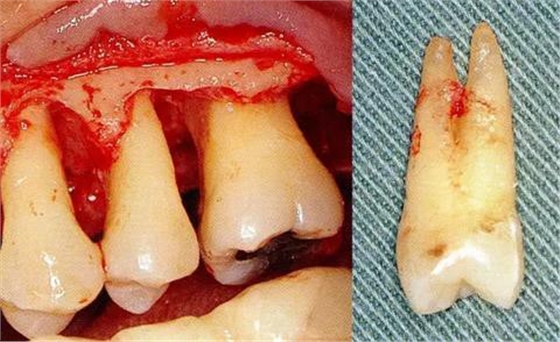

▼圖6-1下頜第一后磨牙的頰舌間存在III度的根分叉病變,預(yù)在進行牙根分割后保留遠中根。

▼圖6-2中下頜第一后磨牙雖然切除了一半,但是遠中根也有2根分根,所以不得已拔除(被拔除遠中根的近中面觀察)。